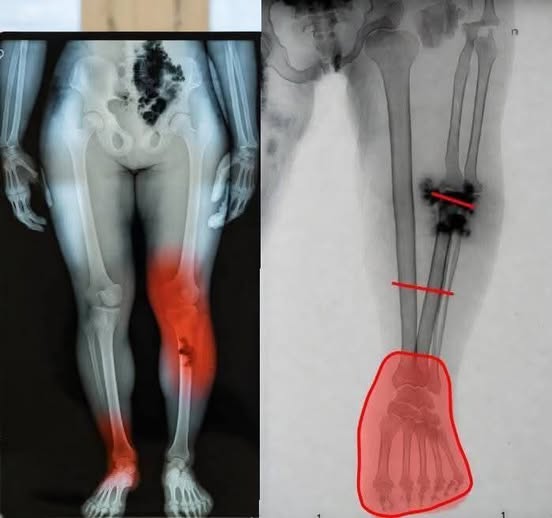

Medical research has identified a small number of myocarditis cases—an inflammation of the heart muscle—following certain mRNA vaccines, particularly among adolescent and young adult males. However, context is critical. These cases are rare, typically mild, and most individuals recover fully with minimal treatment.

Multiple peer-reviewed studies show that the risk of myocarditis from COVID infection itself is significantly higher than the risk associated with vaccination. COVID-19 as a disease has been linked to more severe cardiac complications, including inflammation, blood clots, and long-term heart damage.

In other words, when comparing risks, vaccination reduces overall heart-related danger rather than increasing it.